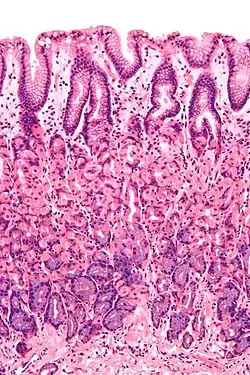

Epithelia and endothelia

Epithelial cells line body surfaces, and are described according to their shape, with three principal shapes: squamous, columnar, and cuboidal.

Epithelium can be arranged in a single layer of cells described as "simple", or more than one layer, described as "stratified". By layer, epithelium is classed as either simple epithelium, only one cell thick (unilayered) or stratified epithelium as stratified squamous epithelium, stratified cuboidal epithelium, and stratified columnar epithelium that are two or more cells thick (multi-layered),[2][3] and both types of layering can be made up of any of the cell shapes.[4] However, when taller simple columnar epithelial cells are viewed in cross section showing several nuclei appearing at different heights, they can be confused with stratified epithelia. This kind of epithelium is therefore described as pseudostratified columnar epithelium.[5]

Mucosa

A mucous membrane or mucosa is a membrane that lines various cavities in the body and covers the surface of internal organs. It consists of one or more layers of epithelial cells overlying a layer of loose connective tissue. It is mostly of endodermal origin and is continuous with the skin at various body openings such as the eyes, ears, inside the nose, inside the mouth, lip, the urethral opening and the anus. Some mucous membranes secrete mucus, a thick protective fluid. The function of the membrane is to stop pathogens and dirt from entering the body and to prevent bodily tissues from becoming dehydrated.